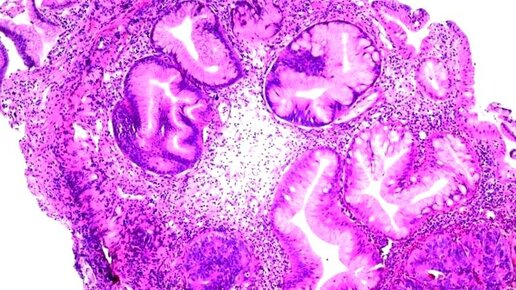

Когда в отчёте по патологии появляется слово аденокарцинома, это может вызвать тревогу и массу вопросов. Что это значит? Насколько это серьёзно? С чего начать и как разговаривать с врачом? Чтобы разговор с медицинской командой был более понятным и конструктивным, важно разобраться в сути термина. Аденокарцинома — это точное медицинское обозначение рака, происходящего из железистых клеток. Железистые клетки находятся по всему телу. Железистые клетки помогают вырабатывать жир на коже, слюну во рту и слизь, которая помогает пище и отходам перемещаться по пищеварительной системе...